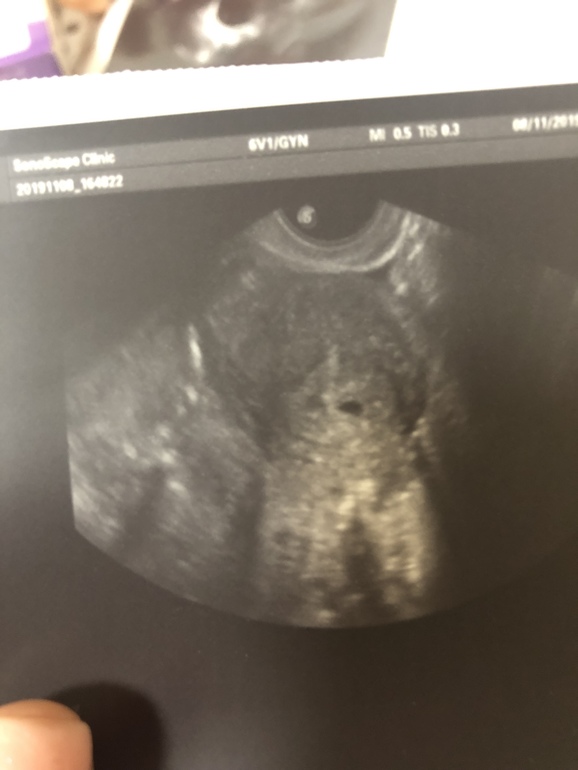

Видно двойню?🙏🏻

Девочки, как вам видится, есть на снимке два плодных яйца??

Ищу поддержки))) Врач сказала, что всё пока под вопросом, маленький срок (4 нед 3 дня)

Ищите поддержки в чем? Только результат с двумя устроит? Чётко видно одно ПЯ. Пока не видно эмбриона, есть вероятность, что разовьются два эмбриона в одном ПЯ, если у вас по генетике были такие близнецы, но это очень редко. У обычных женщин, без генетической предрасположенности, близнецы бывают при двойной овуляции. Но тут все просто: сколько жёлтых тел в яичнике(яичниках)? Два? Если да, то есть вероятность появления второго ПЯ, если нет, то и не будет его.

Чутко вижу одно🤷🏻♀️ а второе просто пятнышко. Плодное яйцо не должно быть с серым оттенком. У меня на первом УЗИ тоже какие то пятнышки были. Но вы не расстраивайтесь, один есть и это уже счастье большое🙏

Плодное чйцо одно и оно с пцстой полостью как бы. Второе там не пустое, это не оно к сожалению

Справа что-то похожее, но меньше. А ЖТ два или одно?

Четко 1плодное яйцо.Растите и развивайтесь.Легкой Б и родов в срок.

Там лишь одно плодное яйцо. Какие два многие видят? Рядом второе эхогенность.

вижу два...ждем с нетерпением от вас новостей)

Пока вижу четкое 1 ПЯ.

Мне кажется видно 2 плодных яйца